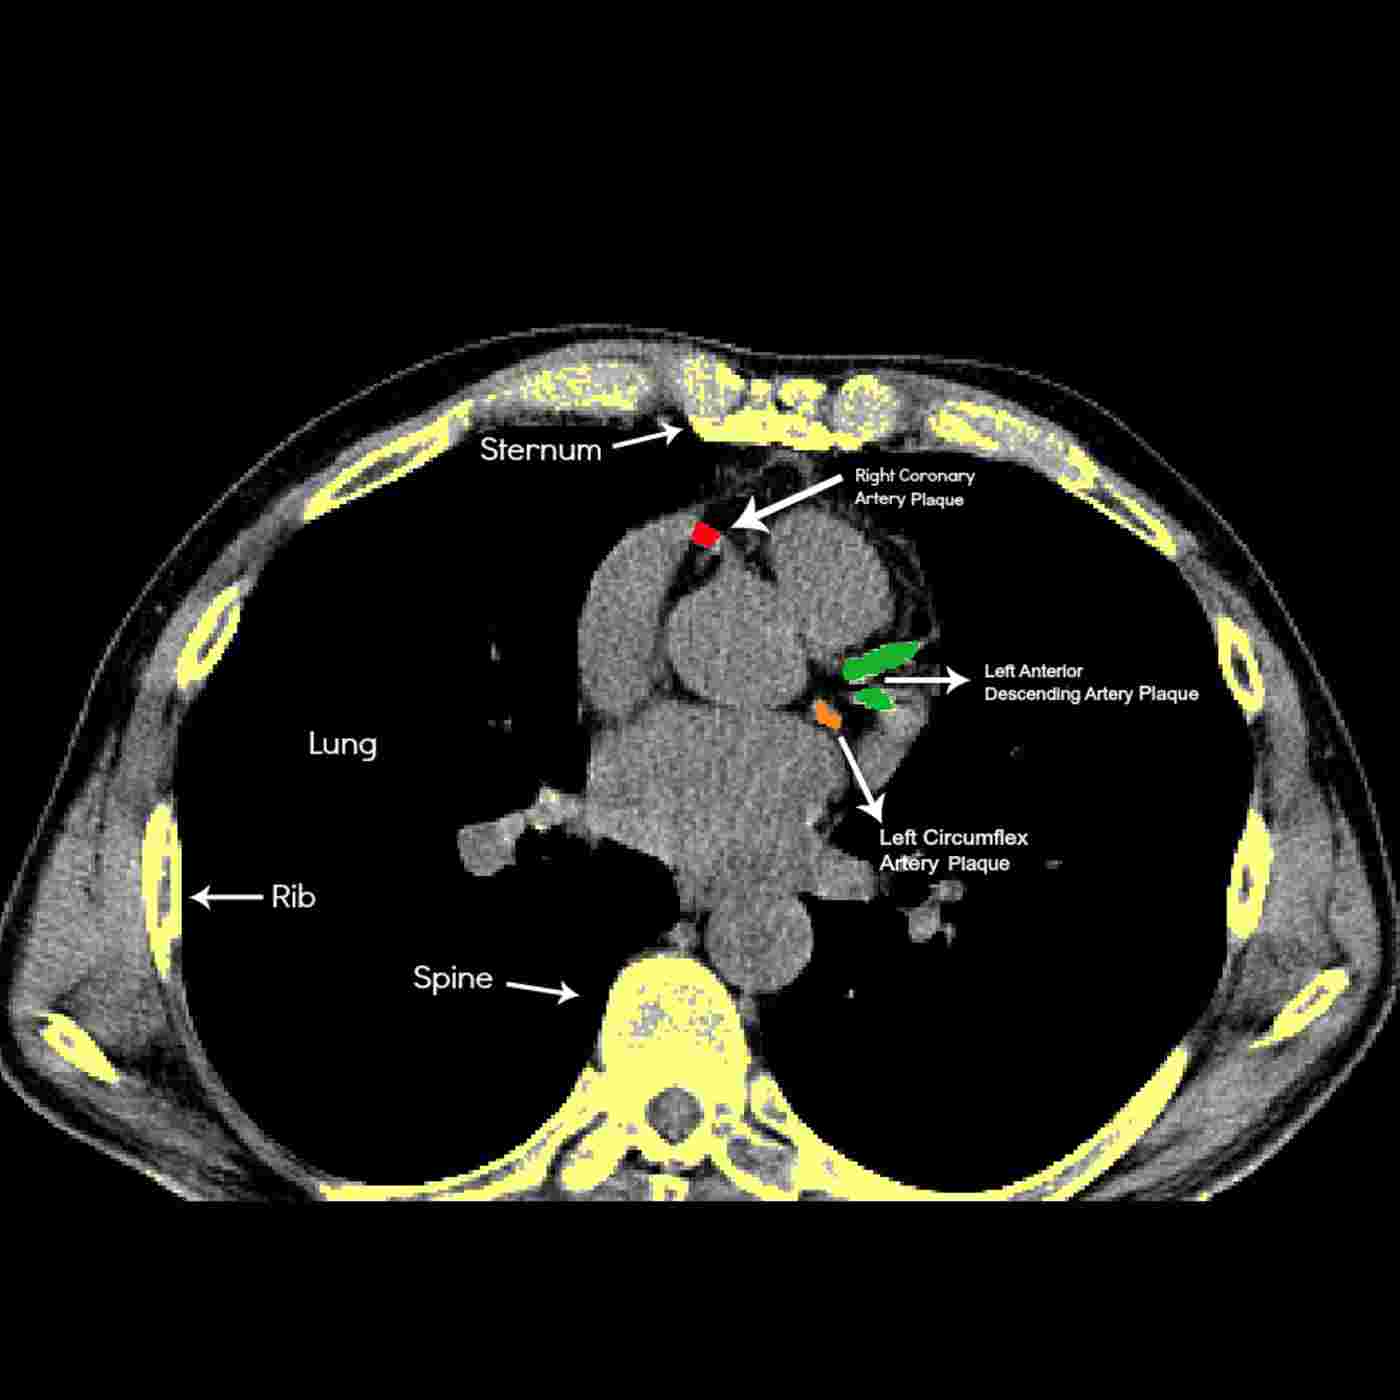

Dr. Blanchet: Who Needs a Heart Scan, When and Where?

This is a quick 20 minute podcast covering everything you need to know about finding and reversing your heart disease. Find out the truth about blockages,stents,and angiograms. Find out what to do about a positive score.